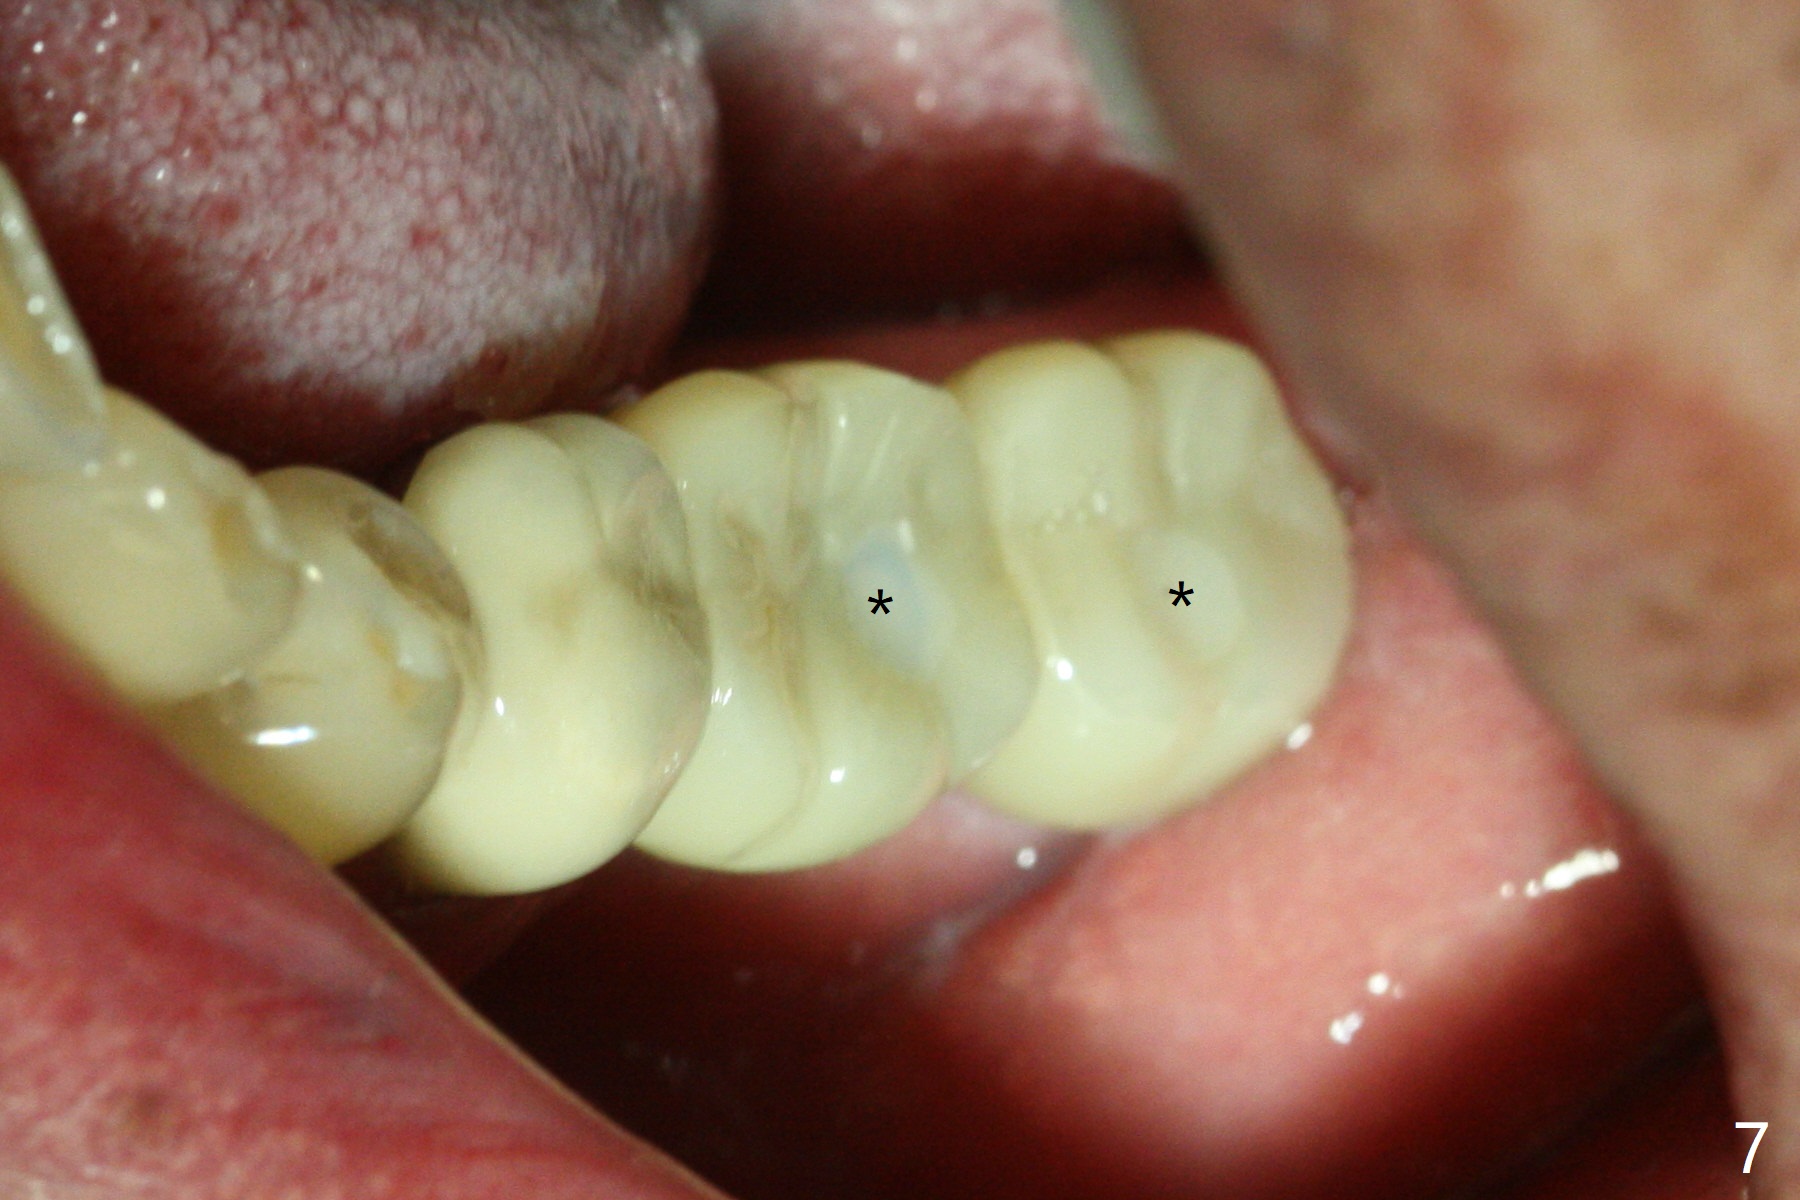

A drawback of placing an implant in the distal socket of the 2nd lower molar is closer to the Inferior Alveolar Canal.  The implants seem to have osteointegrated 4.5 months postop (Fig.5).  While the ridge at #19 appears to be wider than preop (as compared to Fig.1), that at #18 seems to be atrophic 5 months postop (Fig.6 * (1 week post cementation)).  The distal implant placement at #19 may increase possibility of abutment screw loosening during functioning (Fig.7 *).  When the patient returns for periodic exam 1.5 months post cementation, loose contact between the implant crowns is noted (Fig.8).  The bony trabeculae form between the 2 implants crestally 12 months postop, i.e., 7 months post cementation (Fig.9).  The loose contact between the 2 implants is corrected 14 months post cementation.